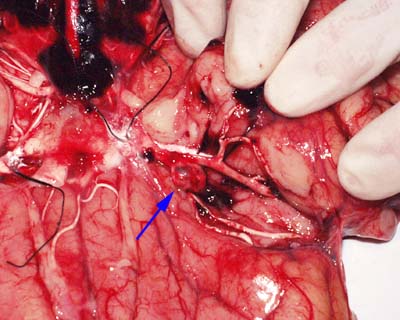

1. Всё ясно. Аневризма относительно большая и сидит на правой средней мозговой артерии. Других аневризм не видно. Смотрю ожидающе на ассистентку. Отпрепарировать сможете сами? Нет я лучше ещё раз посмотрю. mad.gif ОК!

2. Кладу нижнюю половину гол. мозга на препаровочный столик. Беру тонкий зонд с утолщением на конце и тупоконечные ножницы. Подсекаю м.мозговую оболочку между правой височной долей вдоль борозды и лобной долей. Слабой струёй воды промываем кровь. Далее препарирую сосуды тупо концом зонда.

3. Бинго! Вот она аневризма. Всё промываем и делаем фото. Все смеются. Ассистентку опять спасли. Шеф доволен.

Смотрим на часы. Время 11.20

Последний снимок с гистосрезом.

Зачем гисто? Я докладывал этот метод исследования аневизм несколько раз. Ни разу доклад не прошёл без того, чтобы меня не спросили о вымывании тромбов из просвета сосуда контрасным веществом и о вымывании водой тромбов с места разрывов, что делает не возможным диагностику давности разрывов. Мы вынуждены были специально за этим наблюдать. По нашим наблюденям тромб, как на фото остаётся приклеянным к стенке аневризмы и часто конечно в её просвете. Контрастное вещество его точно не вымывает.